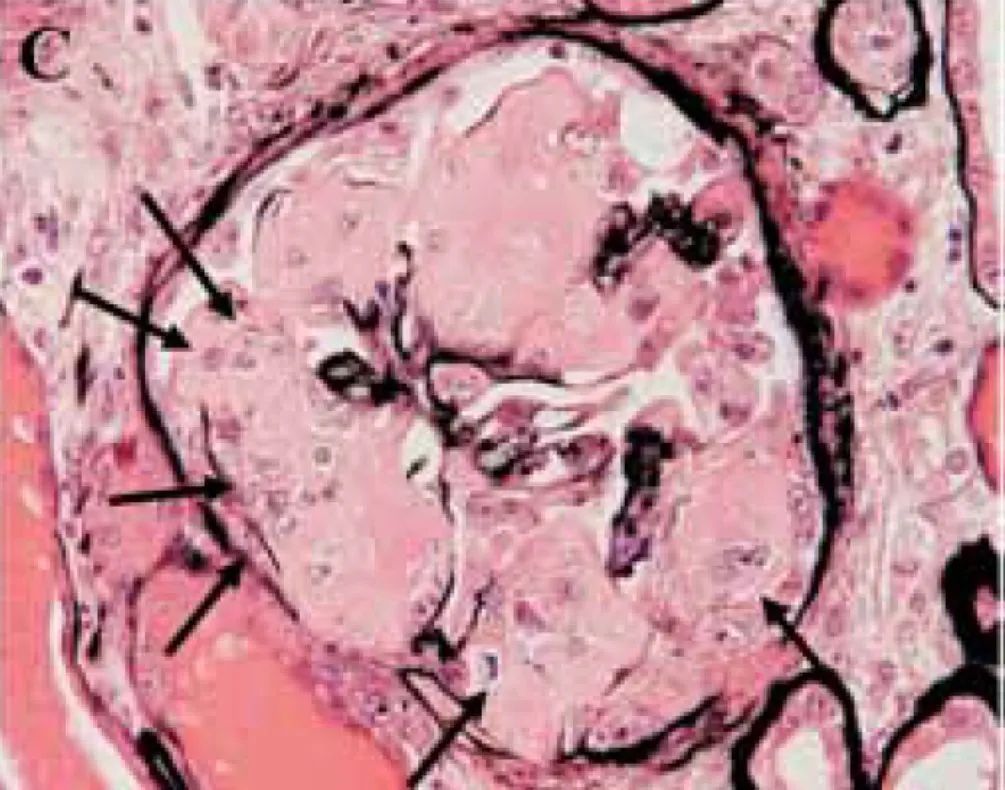

LM:左肾切除标本包含一个13.0 cm的肿瘤,具有透明细胞形态,表达 CA-IX 和 CD10,但不表达 CK7、CD117 或 TFE-3。肿瘤内可见分散的淀粉样沉积物(刚果红染色阳性),AA免疫组化阳性